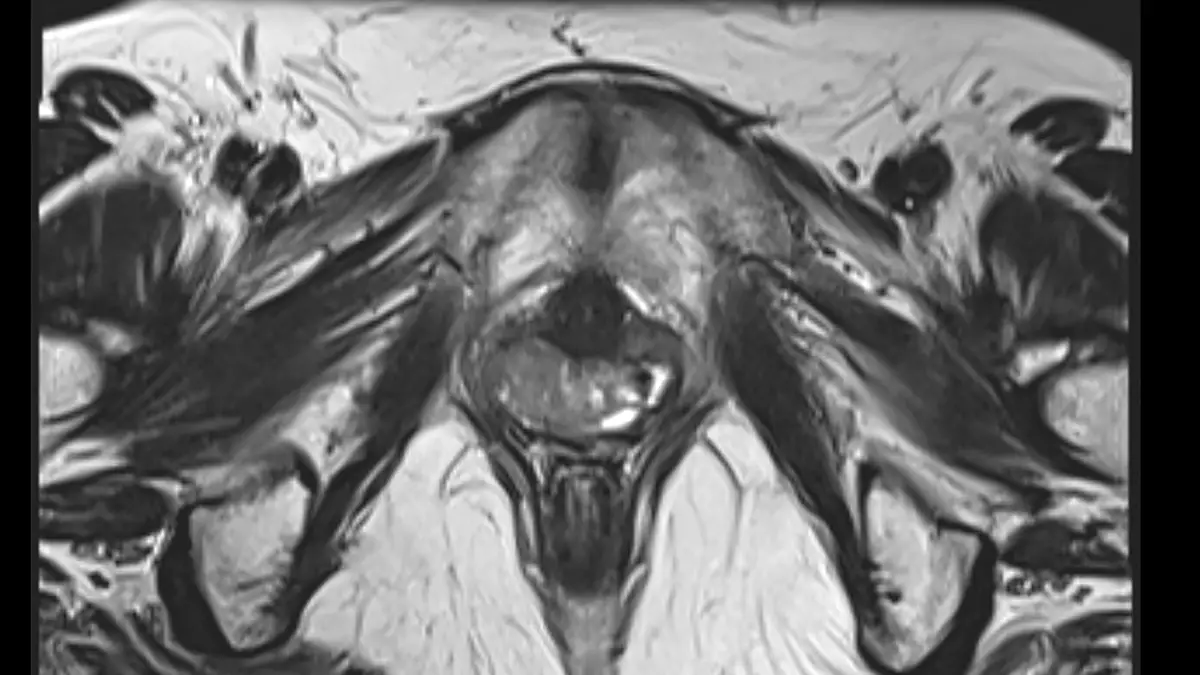

ข้อมูลดังกล่าวถูกเปิดเผย จากฐานข้อมูลการเข้ารับการรักษาในห้องฉุกเฉิน ของคณะกรรมการความปลอดภัยสินค้าอุปโภคบริโภคของอเมริกา เนื่องจากหลายกรณีจำเป็นต้องได้รับการช่วยเหลือทางการแพทย์ กล่าวคือ "มีผู้คนจำนวนไม่น้อยที่ต้องไปโรงพยาบาลในแต่ละปี เนื่องจากมีวัตถุบางอย่างติดค้างอยู่ในอวัยวะเพศ และ ไม่สามารถนำออกมาได้ด้วยตนเอง"

อย่างไรก็ตาม เมื่อพูดถึงสิ่งของที่พบในช่องคลอด รายการกลับยิ่งน่าประหลาดใจยิ่งกว่าเดิม โดยมีรายงานพบสิ่งของต่างๆดังต่อไปนี้ เช่น...